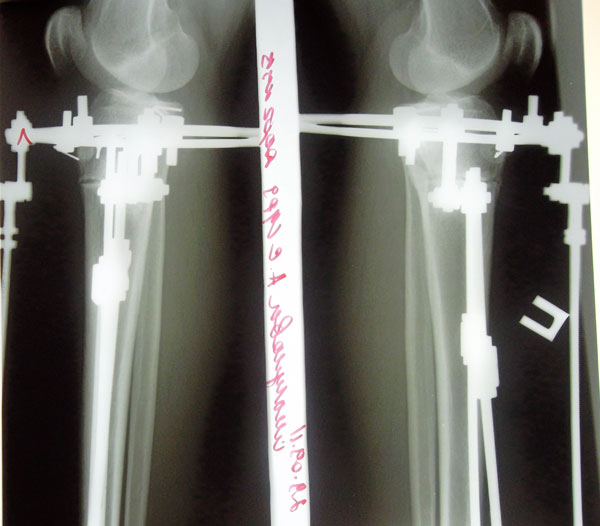

Рентген на 69-ый день с момента ОП. Сегодня была в клинике, проведывала своих подружек, не сдержалась и сделала себе рентгеновский снимок с позволения Николая Николаевича, хотя планировали через неделю. Рентген отличный, можно думать о снятии, но потом придётся поберечься и ограничивать себя в нагрузке ещё недели 2-3. Значит будут страдать посещения занятий в универе, а зачем? Сейчас я хожу совершенно свободно, как здоровый человек и моя походка не привлекает взглядов посторонних глаз. В универе бегаю и летаю по лестничным пролётам, никаких скидок ни в чём мне никто не делает, а мне это даже приятно. Хотя желание освободиться от аппаратов конечно же есть. Чтобы не страдал учебный процесс, с моим доктором со снятием аппаратов решили подождать ещё 2-3 недели.

Сегодня была в клинике, сделала контрольный рентген обеих голеней в 2-х проекциях.

Николай Николаевич посмотрел мои рентгеновские снимки и сказал что можно снимать аппараты. Сращение хорошее.

Мне распустили аппараты для воспитания регенерата(костной мозоли). Через 7-10 дней пойду на снятия аппаратов.